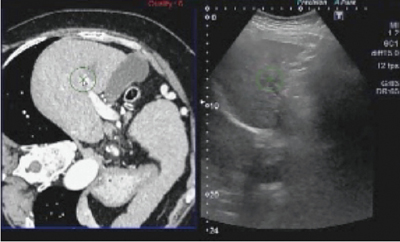

診断から穿刺治療までの全過程をSmart Fusionを用いて行った症例を呈示する(症例2)。腫瘍の検出にはコンベックスプローブ,その後の治療には穿刺用コンベックスプローブを用いている。

本例は,RFA治療部周囲に再発した例で,まず大動脈を軸に描出し,腹腔動脈,上腸間膜動脈の基始部でRegistrationを行った(図15)。腫瘍部付近にある嚢胞を目安に画像を同期させ,腫瘍部分をターゲットとして指定した後,造影を行って,指定部分が早期相で造影されることを確認した。

図15 症例2:71歳,女性,非B非C型,肝硬変,肝S5,HCC,RFA治療部周囲の再発

本症例は,治療部に近接した局所再発で,治療部と再発部の認識は容易ではなかったが,Smart Fusionを用いることで腫瘍部を明瞭に認識することができた。RFA時も,○で囲まれた部分を目安に穿刺し,確実に焼灼することができた。Smart Fusionは,診断から治療までを支援する有用なツールであると言える。